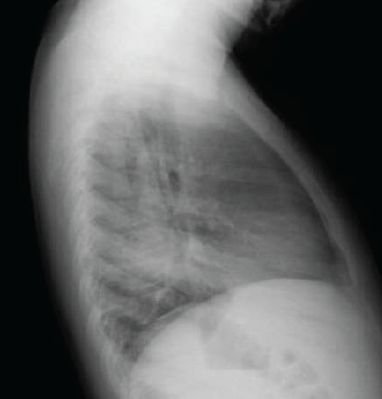

Chest radiographs taken in our ED were remarkable for an opacity in the left lower lobe on posteroanterior view (Figure 3) and lateral view (Figure 4), with significant hyperinflation of the boy’s right lung. Left lateral decubitus view showed an incomplete collapse of the left lung (Figure 5).

Figure 4. Lateral chest radiograph of the boy showing an opacity in the left lower lobe and hyperinflation of the right lung.